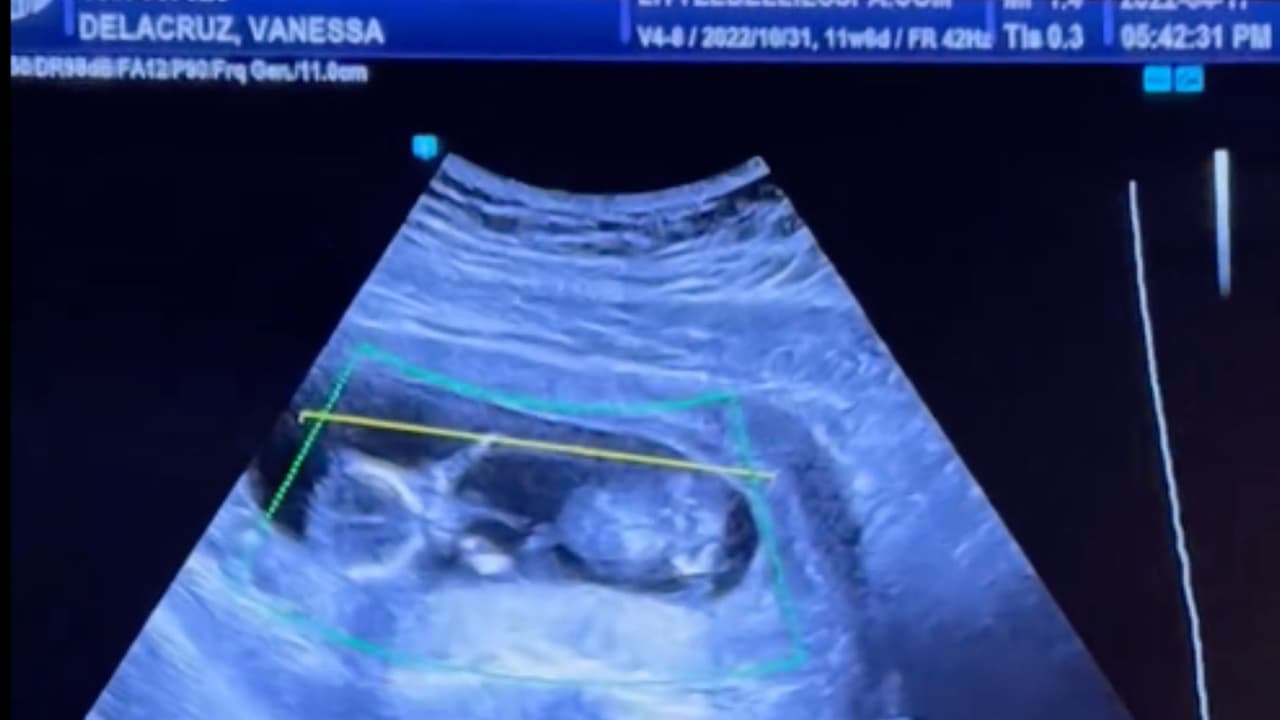

Las víctimas fueron identificadas como Logan De La Cruz, de un año; Vanessa De La Cruz, de 20 años; Karina López, de 33 años; y José López, de 50 años.